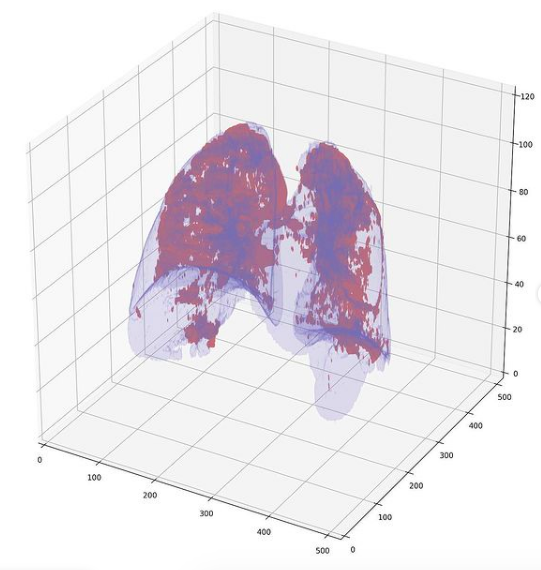

Во время пандемии коронавируса, в 2020 году, система была успешно использована для прикладных задач для выявления признаков вирусной пневмонии коронавируса и узелковых образований в легких.

Тогда компания из Якутского ИТ-парка, разработала программное обеспечение, автоматизирующее процесс выявления пневмонии, ассоциированной с COVID-19, с применением алгоритмов машинного обучения. Принцип второго мнения помогает врачам выявлять коронавирусную пневмонию на ранней стадии. Сначала в пилотном режиме программное обеспечение начало работать в третьей городской больнице Якутска.

Алгоритмы, разработанные командой Сайберия с применением ИИ, позволили автоматизировать диагностический процесс и анализировать данные КТ с высокой точностью. Программное обеспечение автоматизирует процесс принятия решений на основе изображений КТ, и  дает рекомендации врачам обратить внимание на тех, кто из пациентов скорее всего болен коронавирусной пневмонией, а кто страдает от других форм воспаления легких.

Согласно рекомендациям экспертов Московской службы здравоохранения и ВОЗ, в настоящее время для первичной диагностики коронавирусной пневмонии используется компьютерная томография. Основным симптомом этого заболевания является поражение легких в виде интерстициальной пневмонии. Поскольку интерстициальную пневмонию трудно диагностировать даже опытным радиологам, программное обеспечение помогает в раннем выявлении этого заболевания, которое может протекать бессимптомно. При заболевании этим новым видом пневмонии, самым опасным осложнением становится острый респираторный дистресс-синдром. Для эффективного лечения вирусная пневмония должна быть выявлена на ранней стадии.

Базовой деятельностью компании Сайберия является разработка ПО, использующего методы машинного обучения для анализа медизображений КТ, МРТ и рентгеновских снимков. Основанная командой программистов и опытных врачей, организация уже имеет программу скрининга рака легких на основе КТ. Поэтому задача разработки алгоритма для выявления пневмонии, вызванной коронавирусом, стала новым вызовом.